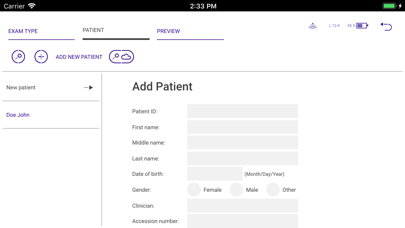

Biim Ultrasound

от Biim Ultrasound Oy